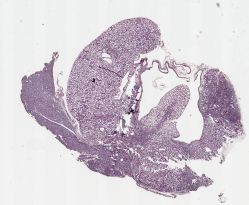

Differential susceptibility to diabetic nephropathy in inbred mice

kidney from DBA/2J diabetic for 25 weeks [Breyer]

Strain

DBA/2J

DBA/2J-5-4

Animal Age

Anatomical Site

H&E Staining

20 X